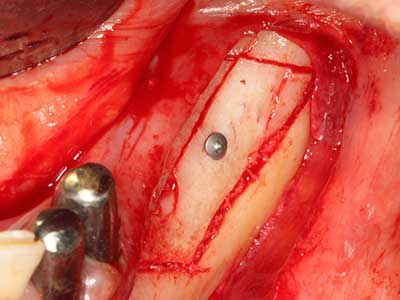

En la extracción de bloques óseos la piezocirugía también presenta ventajas adicionales: Además de la alta precisión en la osteotomía que ya se ha descrito antes, se ha comprobado que el uso de los delgados insertos de sierra resulta especialmente cuidadosas con el hueso. Frente a esto, sobre todo cuando se usan las fresas de Lindemann, cabe esperar pérdidas en la extracción significativamente más altas debido al mayor grosor de la parte frontal del cabezal (Lakshmiganthan, Gokulanathan et al. 2012). La separación basal que se necesita en particular en los injertos de bloque extraídos de forma retromolar se ve facilitada mediante sierras perpendiculares especialmente previstas a tal fin, lo que permite considerar que la cirugía piezoeléctrica es un procedimiento preciso y seguro para la obtención de bloques de hueso en el área retromolar (Happe 2007) (fig. 1-12).

En la cirugía del seno maxilar surgen otros campos de aplicación: En este punto, tras la preparación concéntrica de una tapa ósea de la pared del seno maxilar (que suele tener forma trapezoidal), es posible eliminar patologías y cuerpos extraños del seno maxilar. La tapa ósea se repone después de finalizar la parte intra-antral de la operación y se asegura frente a una posible dislocación mediante cuñas o suturas adaptables.